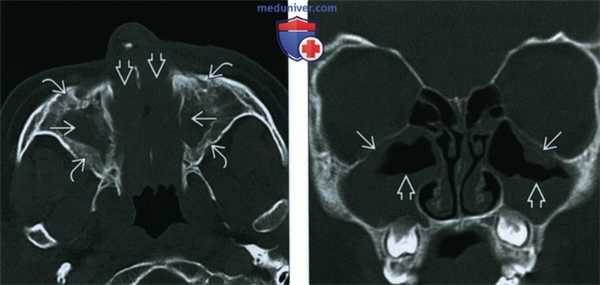

(Слева) Аксиальная ADC-карта у этого же пациента подтверждает рестрикцию диффузии как причину гиперинтенсивного сигнала при MPT DWI. В содержимом левой верхнечелюстной пазухи определяется снижение интенсивности сигнала, в слизистой оболочке на периферии интенсивность сигнала повышена.

(Справа) При аксиальной КТ в костном окне у пациента с хроническим фронтитом определяется утолщение слизистой оболочки, выраженное утолщение стенок пазух, особенно слева. Изменения слева имитируют фиброзную дисплазию.

(Слева) При аксиальной КТ в костном окне у пациента с гранулематозом Вегенера определяются типичные для ХРС изменения верхнечелюаных пазух, пневматизация которых, а также полости носа снижена вследствие наличия мягкотканного компонента. Определяется также остеит стенок пазух.

(Справа) При корональной КТ в костном окне у ребенка с муковисцидозом определяется утолщение слизистой оболочки обеих верхнечелюстных пазух, визуализируются уровни жидкости, подтверждающие присоединение острого инфекционною процесса на фоне хроническою воспаления. Остеит у этого ребенка еще не развился в силу его возраста.